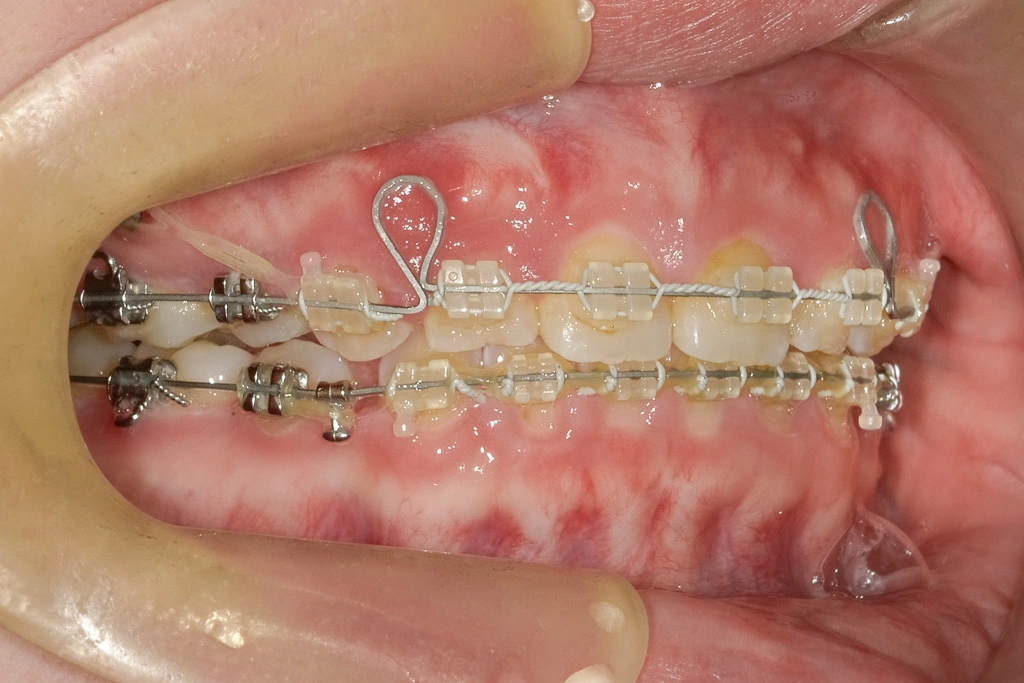

治療開始時

治療内容:第1小臼歯を4本抜歯し、ワイヤータイプの装置で矯正しました。

治療期間:2.5Y

副作用とリスク:痛み・治療後の後戻り・歯根吸収・歯髄壊死・歯肉退縮